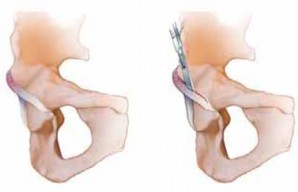

28. A Z-shaped capsulotomy for the right hip and an inverse Z-shaped capsulotomy for the left hip are performed (

TECH FIG 3B

), taking care not to injure labrum and cartilage.

1. The longitudinal limb of the capsulotomy is performed parallel to the axis of the femoral neck, starting at the anterosuperior edge of the stable trochanter. Medially, the capsulotomy is in line with the anterior intertrochanteric line, leaving a cuff of capsular tissue for later reattachment, and extends down toward the lesser trochanter, but stops anterior to it to avoid injury to the MFCA, which runs posterosuperior to the lesser trochanter.

2. The proximal transverse limb of the incision is performed by incising the capsule along the superior acetabular rim until the piriform muscle is reached.

1. These steps keep the limb away from the capsular perforation of the MFCA.

29. The femoral head is dislocated anteriorly to allow inspection of the acetabulum.

1. Flexion and external rotation are used to place the leg in the sterile side bag (

TECH FIG 3C,D

).

2. With traction on a bone hook around the calcar, the femoral head is dislocated, and curved scissors are used to cut the ligamentum capitis femoris.

3. External rotation aids in opening up the anterior joint space and tensioning the ligament for easier trans-section.

30. Lowering the knee lets the femoral head rise automatically out of the surgical site, allowing its full inspection.

1. Two blunt Hohmann retractors are placed around the neck (

TECH FIG 3E

31. To view the acetabulum, the knee is brought higher than the pelvis, and a gentle axial push allows the head to

E F

TECH FIG 3 • A. The trochanteric fragment is mobilized anteriorly. The joint capsule is prepared. The insertion of the piriformis tendon onto the trochanter is intact. B. Schematic of the capsulotomy. C. By flexion and external rotation, the leg is placed in the anterior side bag. This maneuver allows anterior dislocation of the hip. D. Overview across the acetabulum after dislocation of the hip. E. Dislocated femoral head. For better visualization, two blunt Hohmann retractors are placed around the femoral neck. The anterior asphericity and the fibrillated cartilage in the area of impingement are visible. F. Intraoperative view of a left acetabulum. A labral ganglion extending into the soft tissues is visible at the anterosuperior acetabular rim, and the anterosuperior acetabular cartilage flap is seen. come posteriorly, creating enough space to visualize the entire acetabulum.